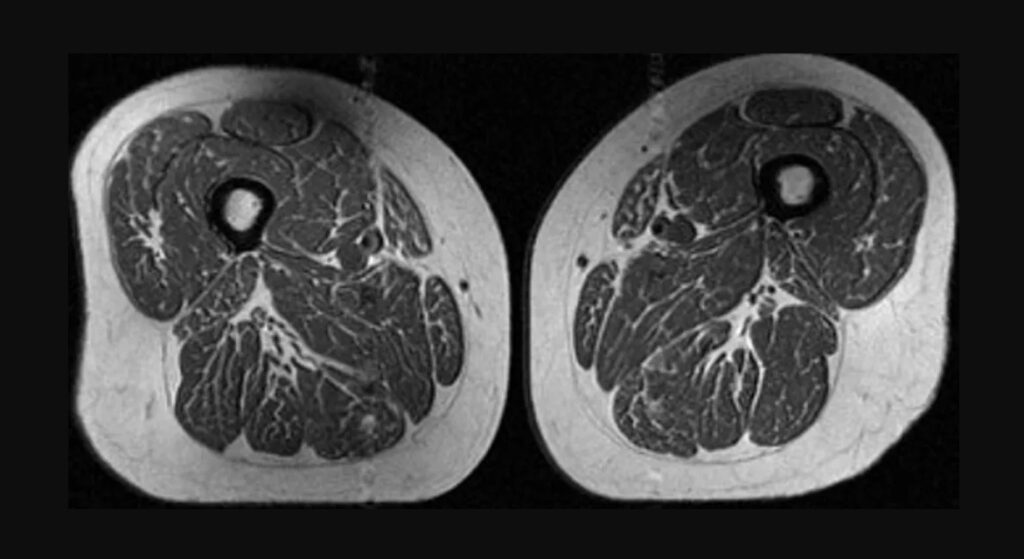

Analiza, bazată pe scanări RMN realizate pe peste 600 de persoane, arată o legătură clară între consumul de alimente ultraprocesate și creșterea grăsimii intramusculare. În unele cazuri, imaginile au relevat mușchi cu un aspect comparat de specialiști cu cel al unei „fripturi marmorate”, din cauza straturilor fine de grăsime infiltrate între fibrele musculare. Cercetătorii au observat că acest fenomen apare chiar și la persoane care nu prezentau semne de osteoartrită, sugerând că degradarea calității musculare începe înainte de apariția simptomelor, scrie CNN.

Grăsimea infiltrată în mușchi afectează capacitatea acestora de a se regenera și reduce forța musculară. În timp, acest proces poate contribui la apariția unor afecțiuni precum osteoartrita genunchiului. Mușchii coapselor sunt esențiali pentru stabilitatea articulațiilor, iar slăbirea lor crește presiunea asupra genunchilor, mai ales în cazul persoanelor supraponderale. Specialiștii avertizează că acest tip de degradare nu este limitat la o zonă a corpului, ci poate afecta și alte grupe musculare, indicând un proces sistemic.

Unul dintre cele mai importante concluzii ale studiului este că efectul nu depinde neapărat de aportul caloric total. Participanții care consumau mai multe alimente ultraprocesate prezentau un nivel mai ridicat de grăsime intramusculară, indiferent de numărul total de calorii ingerate. Această observație sugerează că tipul alimentelor joacă un rol esențial în sănătatea musculară, nu doar cantitatea.